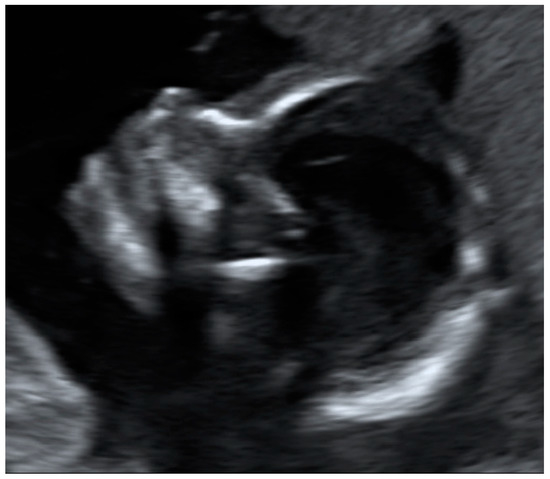

The fetal profile was located satisfactorily by 14.3% of the women in still images (an example is shown in Figure 4) and by 17.9% in the videos.

Figure 4.

Example of an image obtained by a study participant, showing the fetal profile (satisfactory presentation).